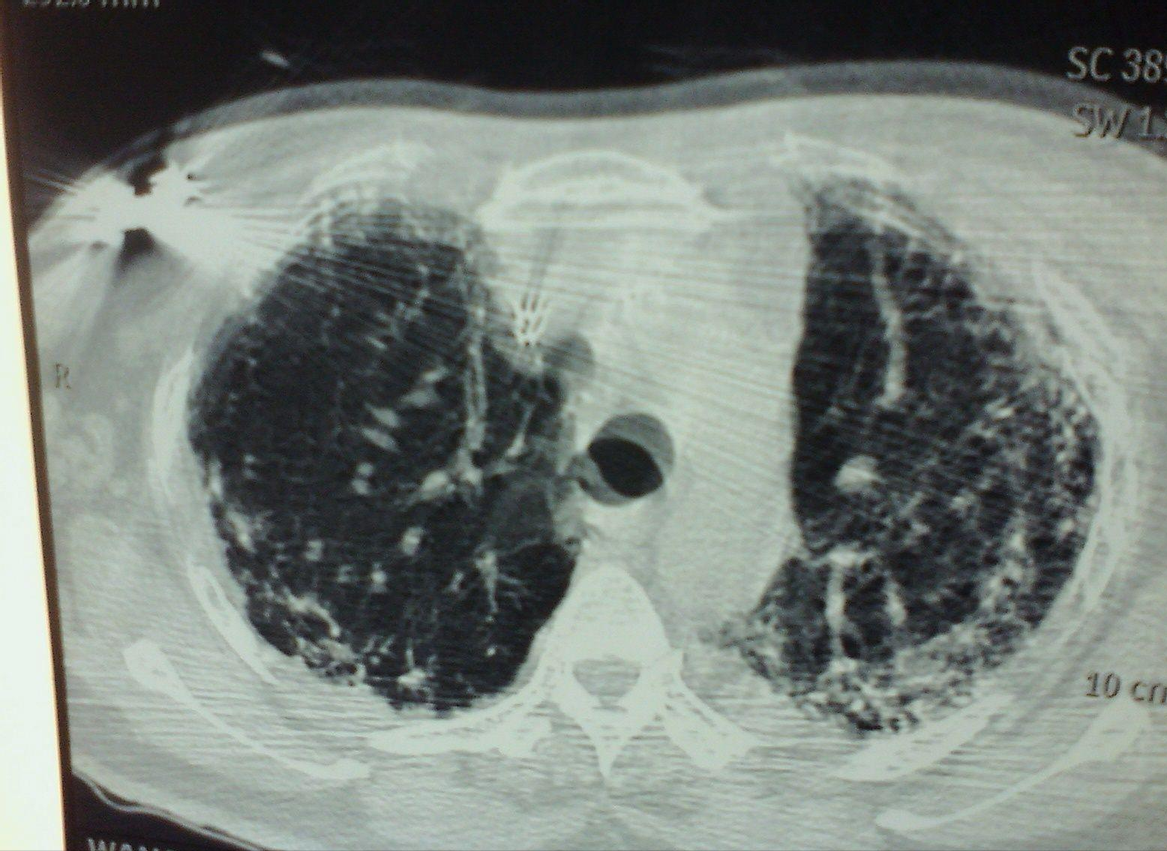

百草枯进入人体后,会快速被患者的肺部吸收,而且是肺脏细胞的主动摄取。几分钟后,患者的肺部组织就会被替换为“纤维”物质,而纤维物质是不具有弹性和交换功能的东西,所以患者最终会死于肺纤维化。

这两年出现的新冠病毒,也是主要攻击患者的肺部,从而造成肺纤维化,引发患者呼吸困难窒息死亡。

从喝入百草枯到肺纤维化不可逆,只需要两分钟的时间,可以说患者几乎没有逆转的机会。